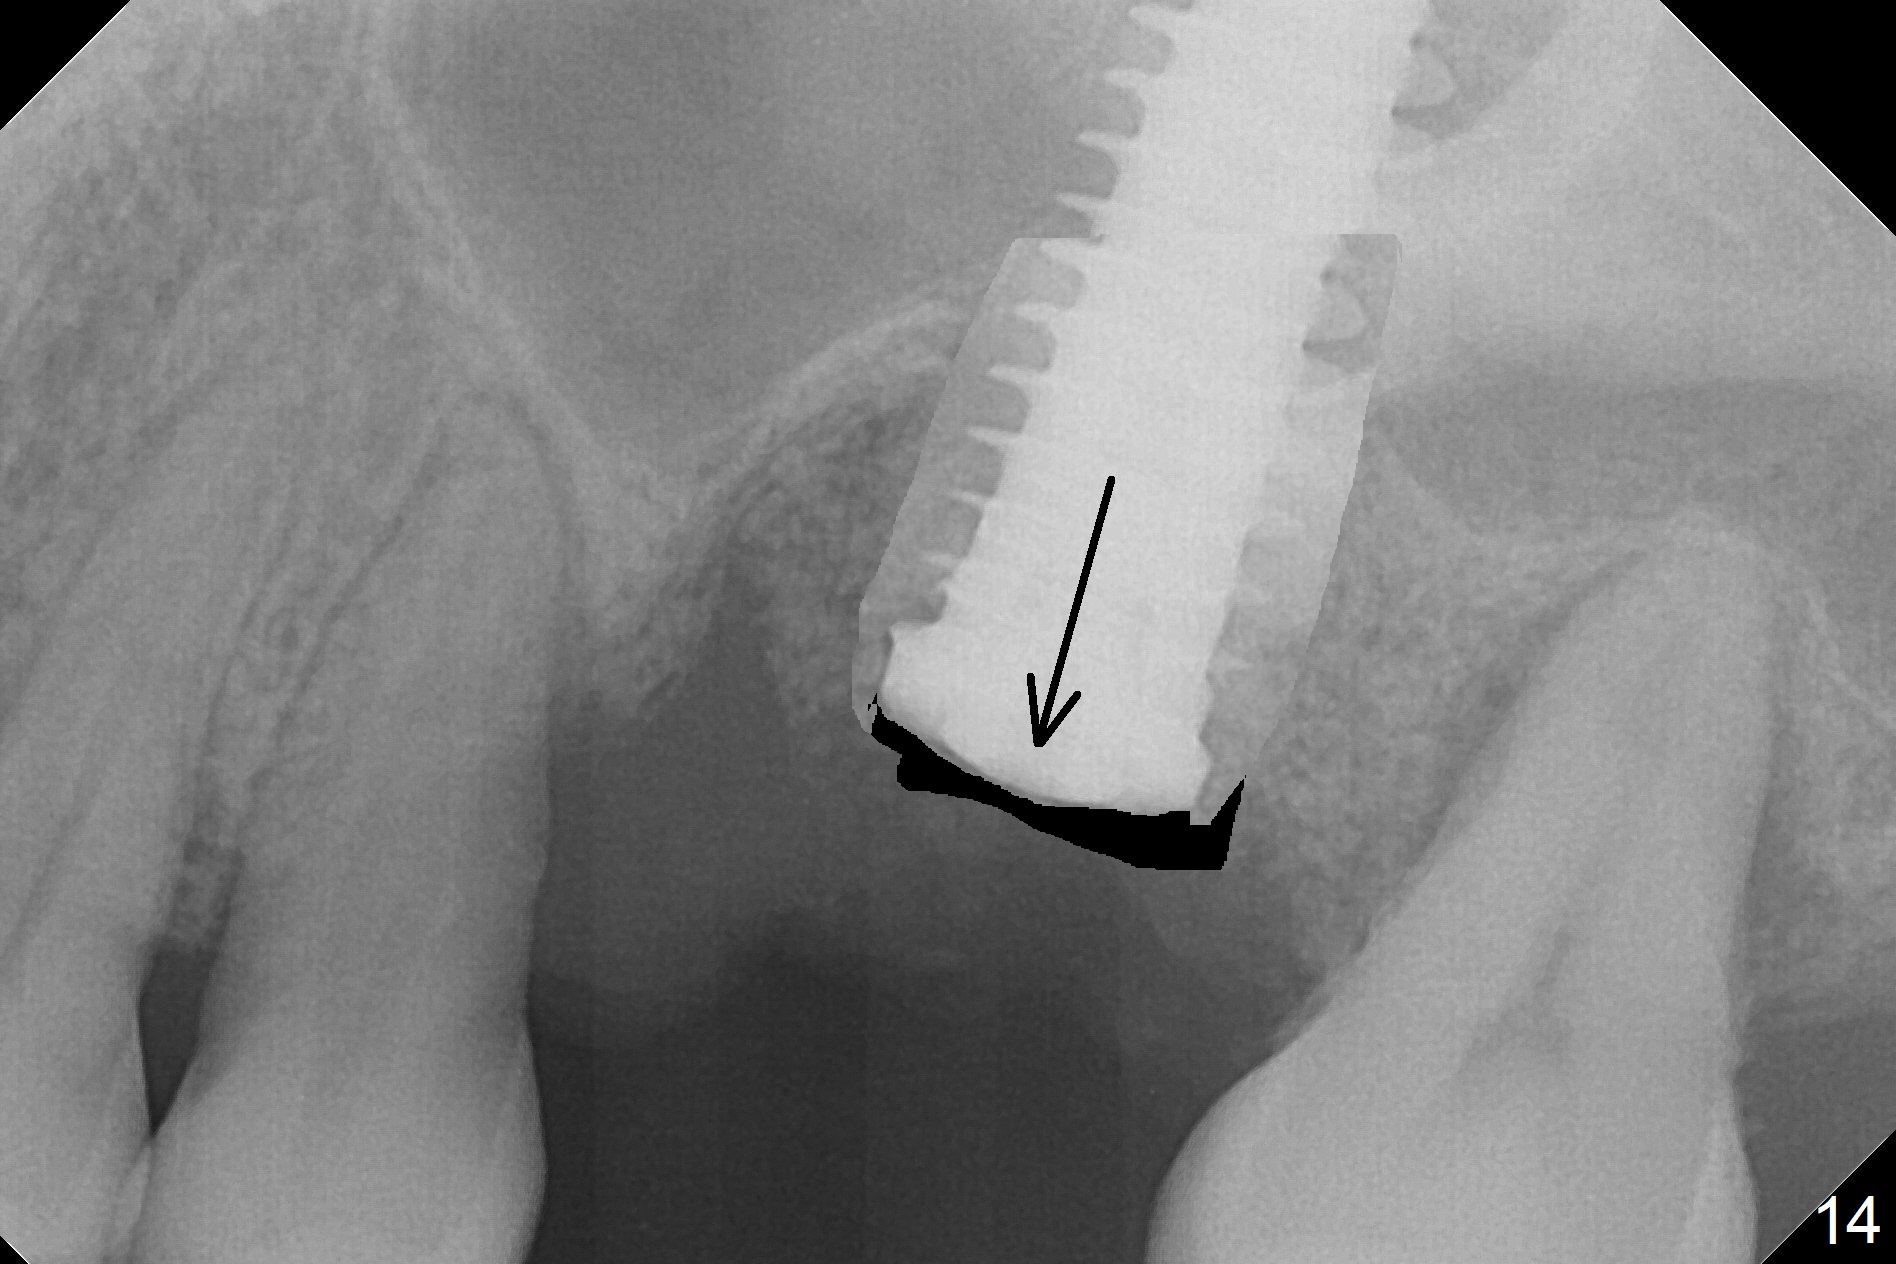

Questions for Dr. Wang: Can we remove the coronal portion of the bone (Fig.13) and back up the implant (Fig.14 arrow) 4-5 months postop for easy restoration?  If it is not a good option, can we produce pair abutments with 5 and 7 mm cuffs?

1.  It seems that the implant was placed deeper than intended, (he had no choice but to do so because of the enlarged osteotomy)

2.  I predict that the bone above the implant will only be about 1-2 mm. In other words, your idea of backing up the implant will only be about 1-2mm possible.

3.  Assuming that 1-2mm of backing up the implant will be sustainable, since stability will still be secure, let heal a month more after backing up, then use cuff 4 abutment to restore.